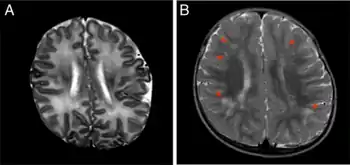

Congenital cytomegalovirus infection can be an important cause of intraventricular hemorrhage and neonatal encephalopathy.[17]